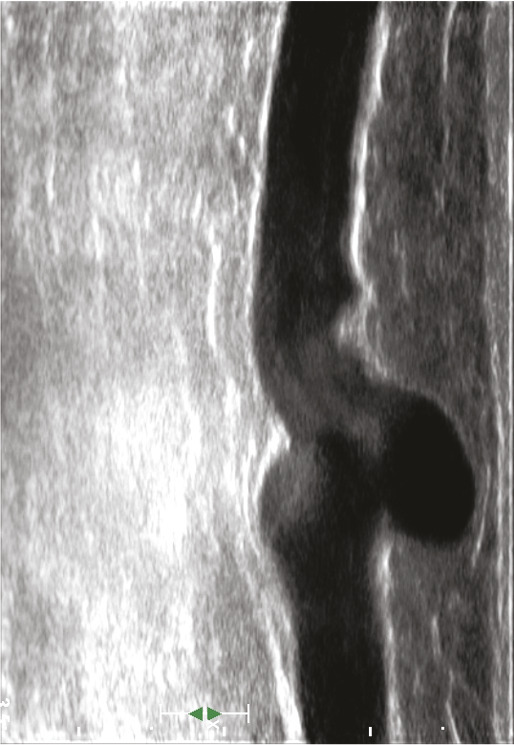

L’échographie en mode B, qui fournit une simple imagerie tissulaire, est utilisée pour identifier le réseau veineux superficiel, analyser les trajets veineux, mesurer le diamètre des veines pathologiques et analyser leur paroi et leur système valvulaire (fig. 12 et 13).